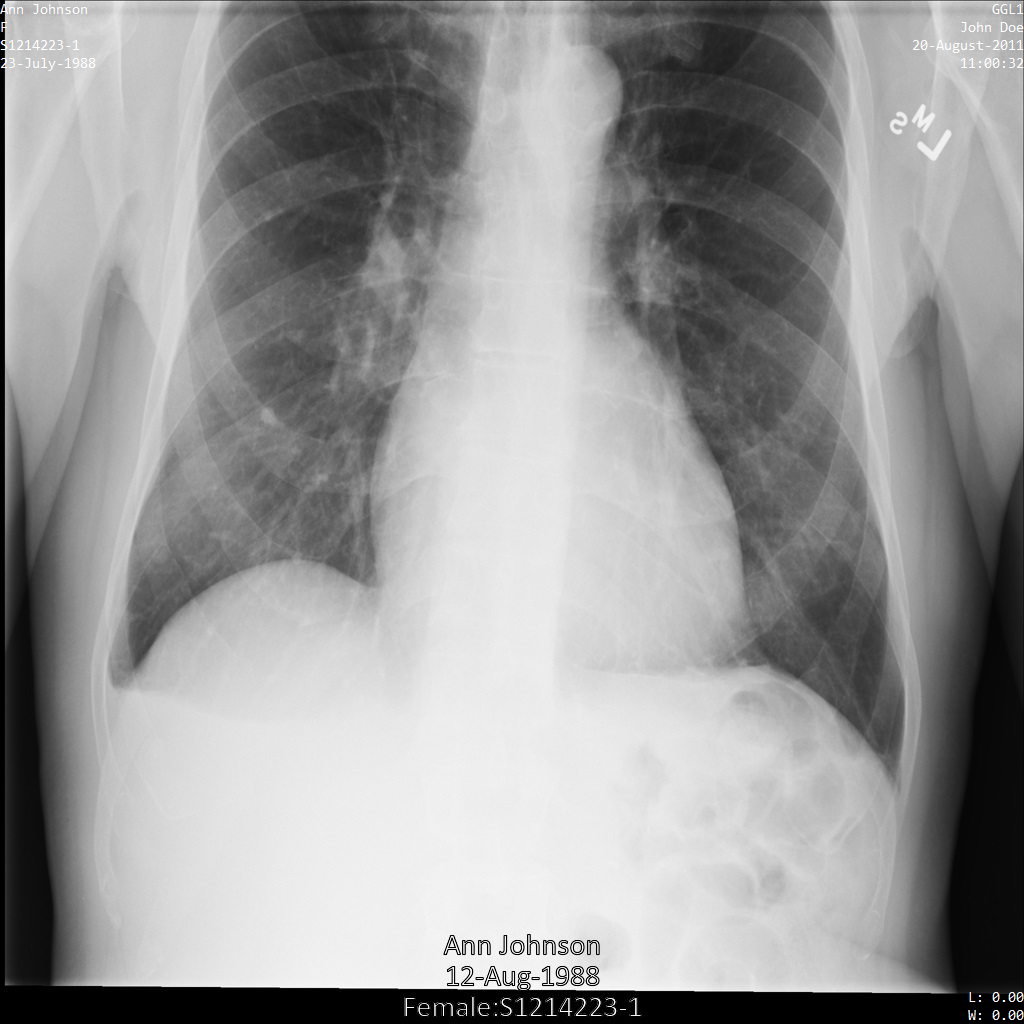

以下の各セクションでは、DICOM データを匿名化するさまざまな方法について、例を示しています。また、それぞれの例で匿名化された出力画像を示しています。各例では、入力として以下の元画像を使用しています。

各匿名化オペレーションからの出力イメージをこの元のイメージと比較して、オペレーションの効果を確認できます。

次の画像は、患者の X 線を秘匿化していない状態を示しています。

REDACT_SENSITIVE_TEXT オプションを使用して Cloud Healthcare API に画像を送信すると、画像は次のように表示されます。

次のことを確認できます。

- 画像の左下にある

PERSON_NAMEが秘匿化された - 画像の左下にある

DATEが秘匿化された

患者の性別は、デフォルトの DICOM infoTypes に従って機密テキストと見なされないため、秘匿化されませんでした。